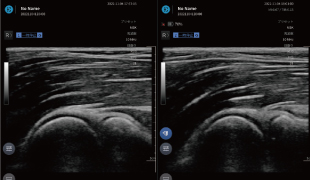

2画面機能

左右にエコー画像を並べて表示することが可能。健側・患側のリアルタイムな比較はもちろん、過去のエコー画像を表示して現在の画像と比較することによる治療の評価も可能です。